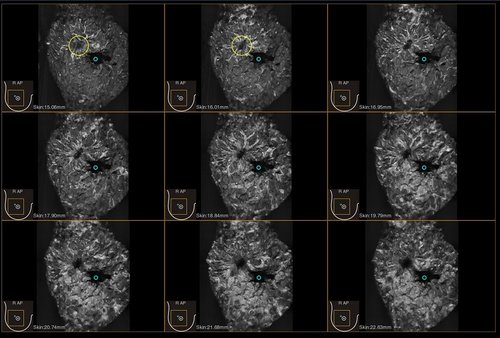

Das IBUS 60 ist ein intelligentes Brust-Vollvolumen-Ultraschallsystem der Marke SIUI.

Das IBUS 60 zeichnet sich durch Sicherheit und Komfort aus. Es bietet ein hochauflösendes Bild und reduziert somit Fehldiagnosen, was ideal für die Brustuntersuchung ist, insbesondere bei einer dichten Brust.

• Nanopure Technologie zur Specklereduzierung